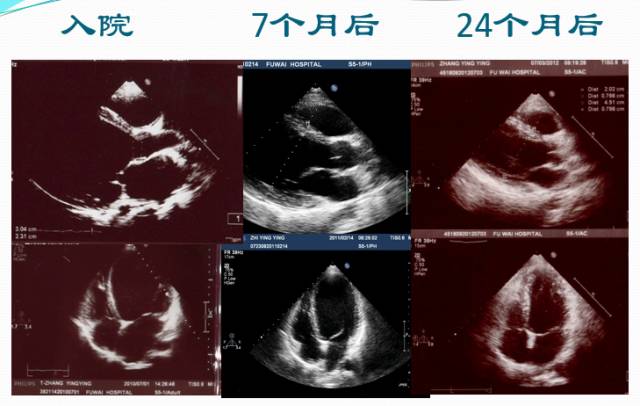

超声心动图

►超声心动:LA 36mm,LV 86mm,LVEF 20%,RV 24mm

►左房轻度增大,左室明显扩大成球形,左室壁弥漫性运动减弱,右房室不大,二尖瓣中大量返流

► 7月后复查:心脏缩小,心功能好转

► 2年后病情平稳,复查超声心动图、NT-proBNP等大致正常。仅口服比索洛尔10mg qd+贝那普利5mg qd

► 3年后复查HOLTER:频发房早32925次,短阵房速。 患者心率控制在70-90bpm,超声心动图依然大致正常。未再出现胸闷,浮肿等症状。

► 6年内多次复查,UCG正常。无心衰症状。

► NT-proBNP 8787.94pg/ml(入院时)→540.1pg/ml(1年后)→ 378.4pg/ml(2年后),后多次复查均正常

超声心动图演变